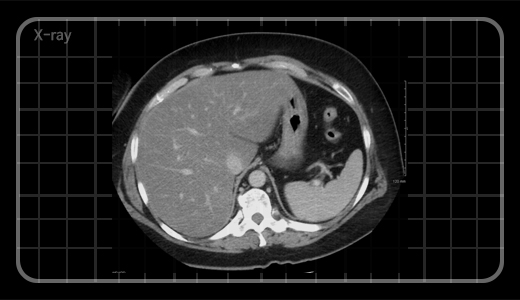

이 환자는 간경화 환자로, 그 정도가 심해 식도정맥류와 간비대 증상을 보였으며 특징적으로 심한 무릎관절통을 호소하던 분이셨습니다. 근육이 찢어질 듯 아프며, 그 통증으로 수면까지 방해된다고 하셨죠. 한의학에서는 간이 근육을 지배한다고 하죠? 한약은 간 손상을 유발한다는 관념을 깨고 사전에 각종 검사를 통해 환자의 상태를 확인한 후 한약을 복용시켰습니다. 2009년 8월부터 2010년 3월까지 7개월간 꾸준히 한약 섭취 후, 하지부의 통증과 마목감이 사라졌을 뿐만 아니라, 정맥류로 인한 혈전이 사라지는 결과를 얻을 수 있었습니다.

이와 같은 간경화를 한약으로 치료한 실제 임상 사례처럼, 우리는 한약이 간과 신장을 손상시킨다는 관념에 두려워하지 말고 한약이 간 및 신장에 손상을 주지 않는다는 믿음을 가지고 환자를 치료해야 합니다.

한약이 간/신장독성이 없다는 연구 결과만 제시하며 방어만 할 것이 아니라 의사들이 현재 하지 못하는 영역에 대해 도전을 해야 합니다. 예를 들어 간 이식 대기 환자의 경우, 간 이식을 기다리다 중도에 사망하는 경우가 매우 많습니다. 그 환자들에게 한약을 통해 간 기능을 일정 수준 이상 복구시켜 실제 대기 시간을 늘릴 수 있다면 간 이식에 성공하여 생존할 수 있겠지요. 이처럼 한약 병행 치료가 가능하다면 전 세계 대기 환자 몇백만 명이 몰려 우리나라는 간이식 허브로 발전할 수도 있습니다. 물론 이와 같은 치료가 가능하게 하려면 인체에 대한 깊은 이해와 경험, 그리고 실력을 동반해야 합니다. 한의학적 차원뿐만이 아니라 서양 의학적 지식 또한 적극적으로 포용하면서 한약의 부작용을 두려워하는 방어적 자세가 아닌 치료할 수 있다는 공격적인 자세로 의학 의 논리에 대응해야 합니다.